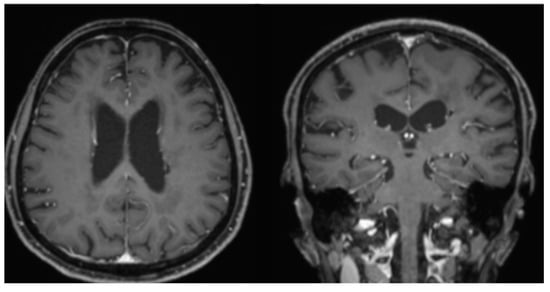

2. Case Report